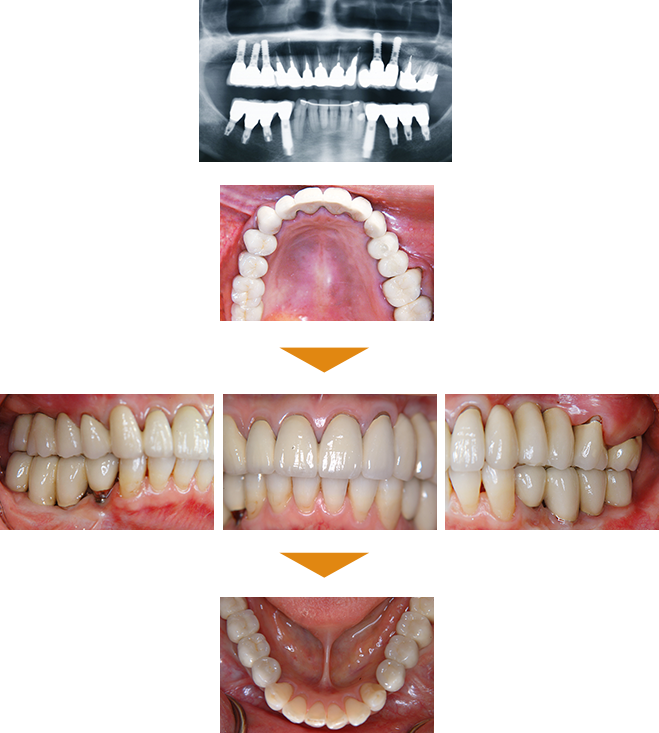

症例と経年後の状態紹介

| 治療本数 | 上顎:5本 下顎:8本 |

|---|

| 治療期間 | 8カ月 |

|---|

| 費用 | 合計 6,500,000円(税込) |

BEFORE

この患者様の治療には、初診から最終補綴物装着までに約半年の治療を要しました。当時、最先端といわれていた治療も併用して、治療に臨みました。

患者様は、相当な額の治療費をお支払いくださり、最後まで根気よく受診してくださいました。

AFTER

最終補綴物装着の日に、患者様に「治療は、今日から始まりですよ。」と伝えると、『今日で終わりではないのか?』という不思議そうな表情をされていらっしゃいました。

治療後16年経過

このケースがどうして16年経過しても、治療終了時と大差なく状態を維持できているかというと、ズバリ「定期的なメインテナンス」の一言に尽きます。

もし、3カ月に一度、メインテナンスに来院されていなければ、間違いなく再度新たな治療介入が必要になっていたことでしょう。これは、疑いの予知はありません。

メインテナンス時に行うことは、PMTCと咬合調整が主体です。また、1年に一度のレントゲン撮影を行い、骨レベルの変化やその他の問題が無いかの確認をします。

16年治療介入の必要なく、過ごしてこられたのは、きちんとメインテナンスに来院されたことが主たる要因です。

長期的な予後を左右するものは、ズバリ定期的なメインテナンスが鍵と言わざるを得ません。

皆様も歯を入れたら終わりではなく、治療を終えたら、定期的なメインテナンスをお受けになることをおすすめいたします。『メインテナンスは、歯医者が金儲けですすめている!』といった言葉を良く耳にしますが、決してそうではありません。メインテナンスを行わず放置してしまうと、必ず治療介入を強いられることになります。それは再度多額の治療費が発生する事態となり、そちらの方が歯医者にとっては、金儲けになります。しかし、我々は金儲けで歯科医業を営んでいる訳ではないのです。

患者様の色々な痛みや悩みを排除して、美味しい食事が摂れて、いつも笑顔を絶やさない日常を送れる様になっていただきたいという倫理に基づいて歯科医業を営んでいるのです。

どうかこのことをご理解いただいた上で、治療終了後にメインテナンスをお受けになっていただきたいと切望いたします。